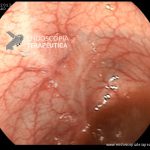

- Doença de Crohn em remissão – cicatriz